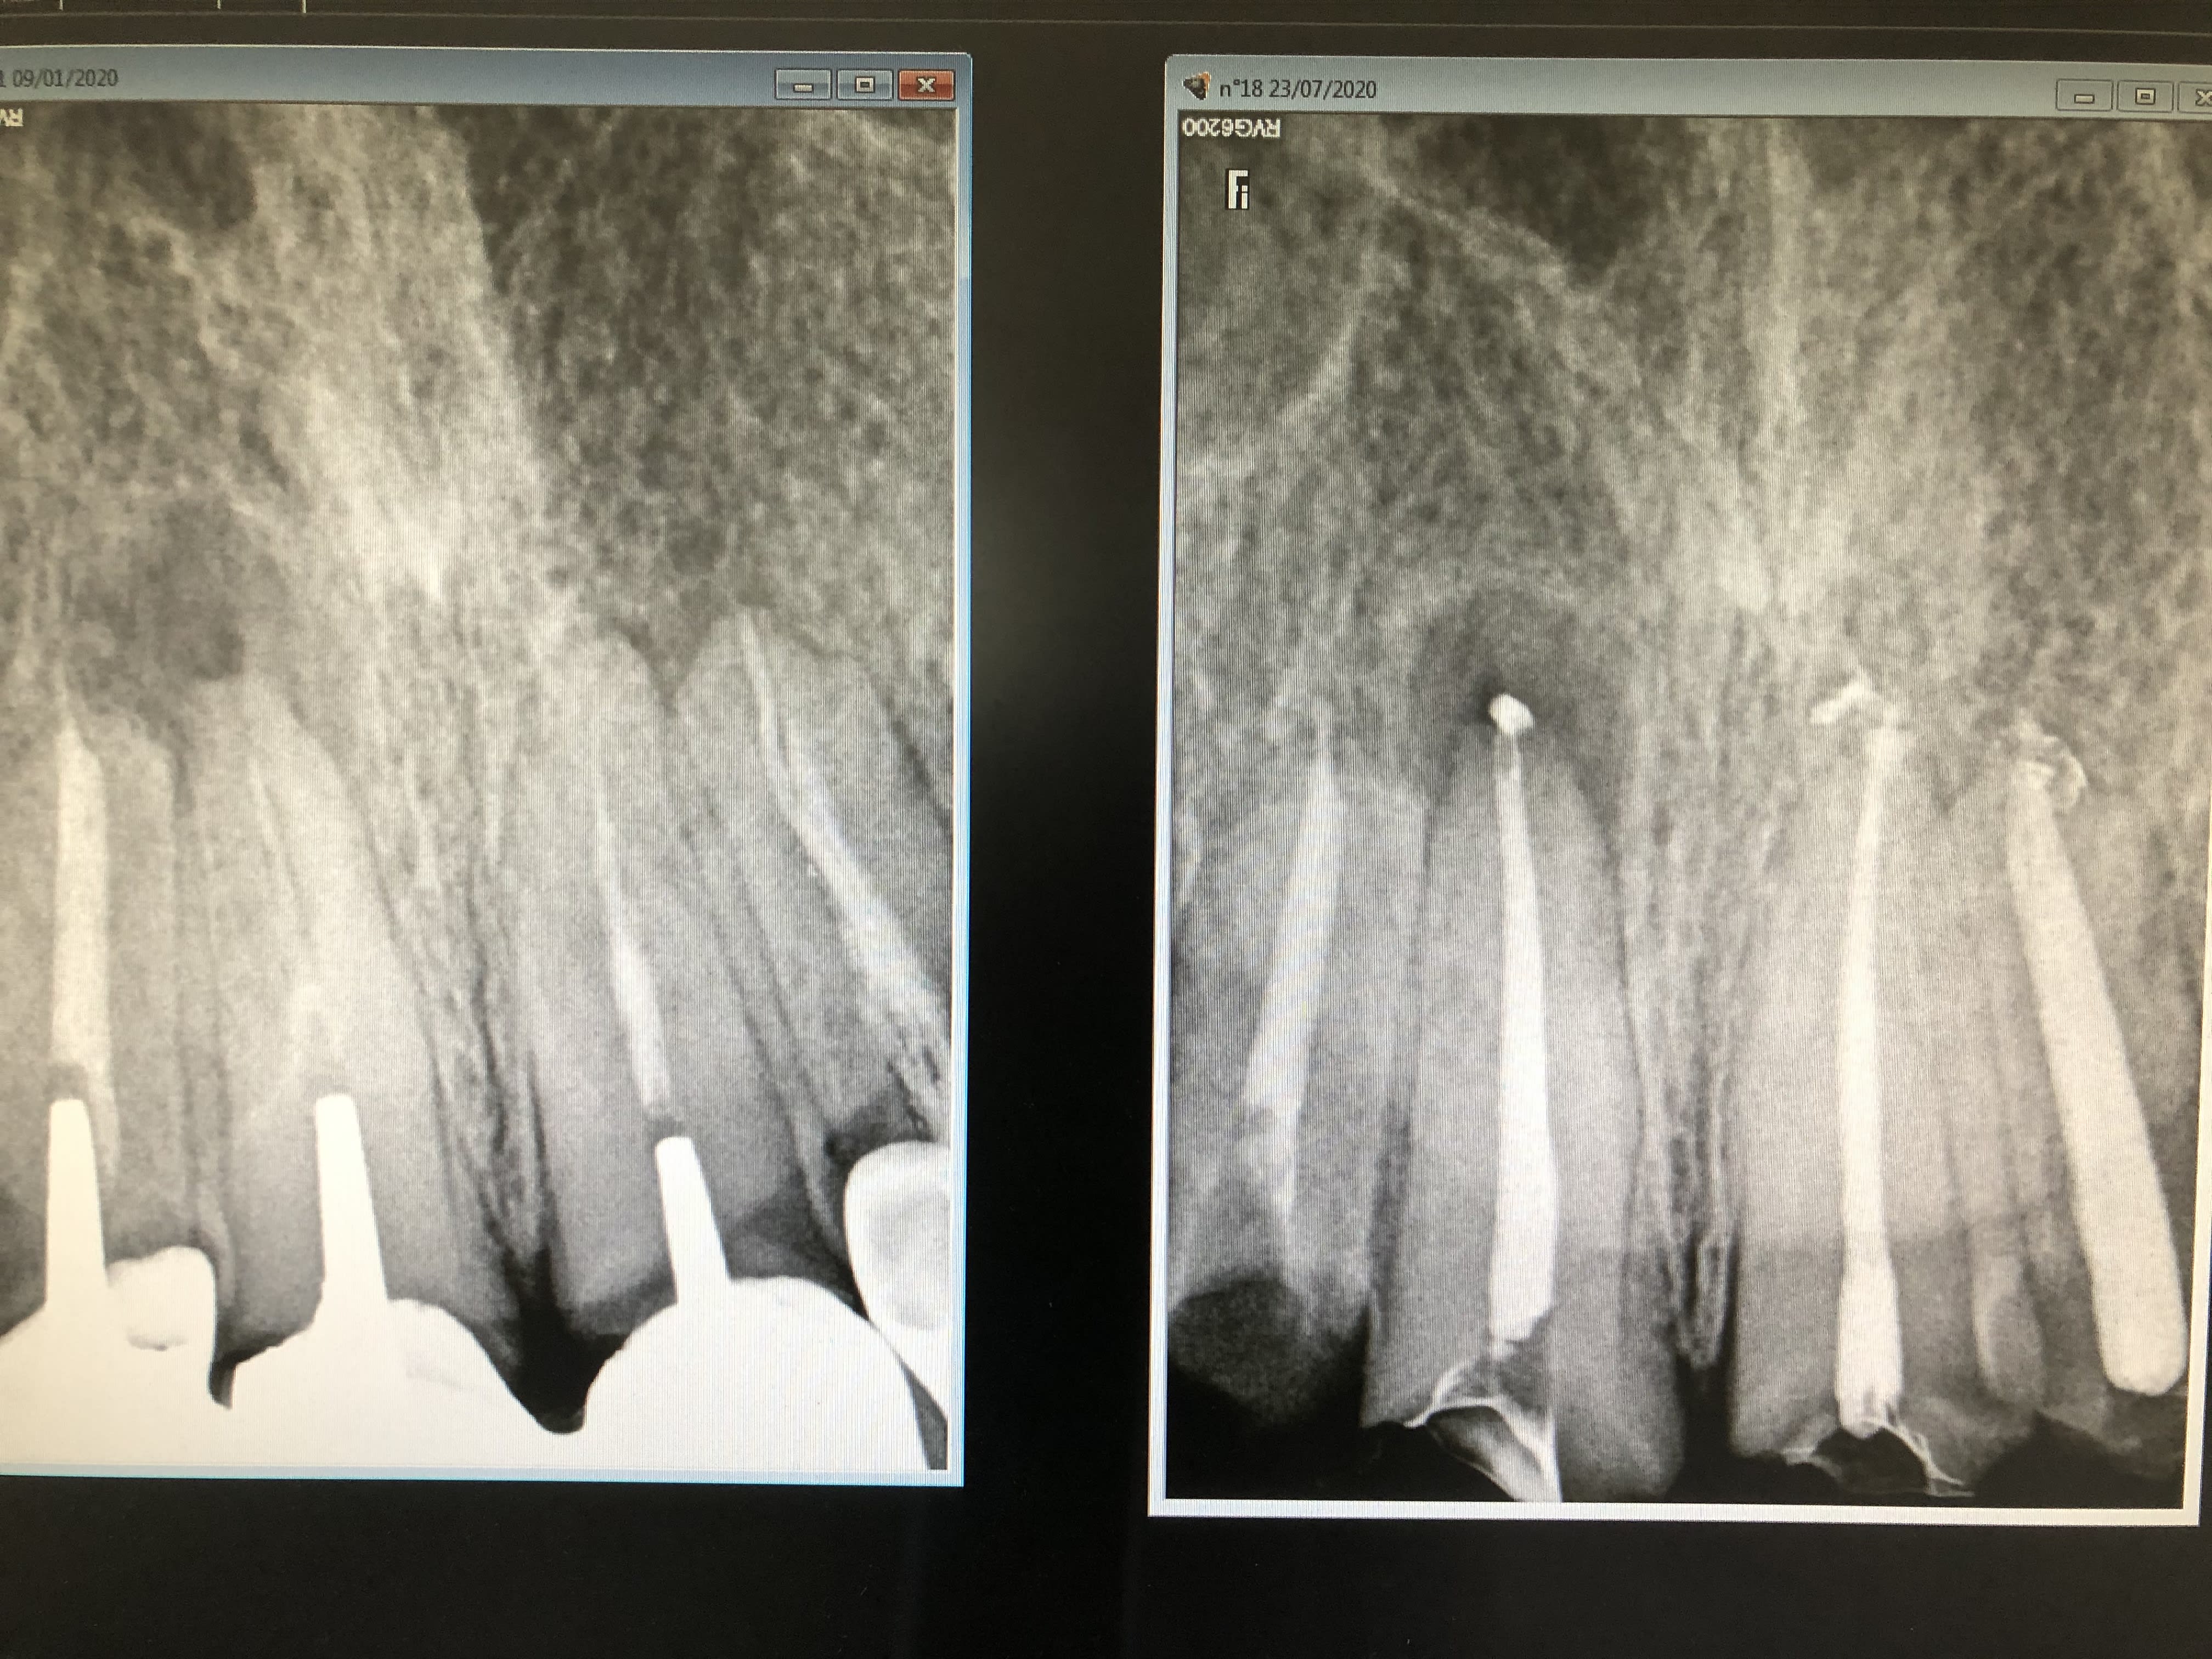

La radio de l’année. A force ça devait bien arriver.

Reste plus qu’à cicatriser, et ça c’est une autre histoire

ç est tout le pb des images radio endodontiques .

on les a créé pour ça , pour que l on puisse porter un jugement administratif sur un travail effectué qui ne voit pas . voilà pourquoi il a fallu que ce soit radio opaque .

à partir de là , avec de la mauvaise foi , tu peux raconter n importe quoi au vu d une radio , et il y en a qui ne s en privent pas .

combien de temps dure un ttt , et combien de temps dure l obturation ? quand on réfléchi à ça on ferme sa gueule .

Je ne vois pas trop l’intérêt de cette radio de cas simples ni de la ramener sur le travail sans champ qui plus est par les temps qui courent.